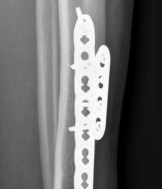

When a diaphyseal fracture propagates into the distal articular block, the injury transcends the typical treatment algorithms reserved for isolated tibial shaft fractures. Intramedullary nailing, the gold standard for diaphyseal fractures, becomes fraught with complications such as articular malreduction, propagation of intra-articular fracture lines, and inadequate distal fixation. Therefore, plate fixation—often utilizing minimally invasive percutaneous plate osteosynthesis (MIPPO) techniques—emerges as the primary definitive treatment modality. In the setting of an AO/OTA 43C3.3 fracture, where the articular surface is multifragmentary and completely dissociated from the diaphysis, the surgeon must meticulously reconstruct the joint surface before bridging the diaphyseal segment.

With the articular surface reconstituted, the surgeon's focus shifts to bridging the complex metaphyseal-diaphyseal dissociation. A pre-contoured anatomical locking plate is slid submuscularly or subcutaneously along the diaphysis using a MIPPO technique. The plate is positioned on the anterolateral or medial surface, depending on the preoperative plan and soft tissue constraints.

The distal portion of the plate is secured to the reconstructed articular block. It is imperative that the distal locking screws are placed parallel to the joint space, forming a rigid subchondral raft that supports the articular cartilage. Fluoroscopy is utilized extensively to ensure no screws have penetrated the joint. Once the distal block is secured to the plate, the diaphyseal segment is aligned. Length, alignment, and rotation are restored using manual traction or the femoral distractor. The proximal portion of the plate is then secured to the diaphysis using a combination of non-locking screws (to pull the bone to the plate) and locking screws (to create a fixed-angle construct). The working length of the plate is maximized by leaving several screw holes empty over the zone of comminution, promoting secondary bone healing.

More recently, the literature has focused on the biomechanics and clinical outcomes of Minimally Invasive Percutaneous Plate Osteosynthesis (MIPPO). Studies by Borg et al. (2004) and Helfet et al. have demonstrated that preserving the extraosseous blood supply through submuscular plating techniques yields high union rates and minimizes soft tissue stripping. Current clinical guidelines strongly advocate for the integration of CT-based preoperative planning, staged management for high-energy injuries, and the use of anatomically contoured locking plates applied via MIPPO techniques to optimize both biological healing and mechanical stability in these devastating injuries.